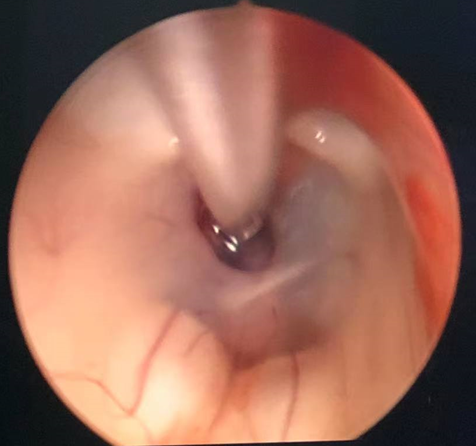

诊治过程:结合患者临床表现及影像学表现,初步诊断考虑为三脑室后部胶质瘤合并梗阻性脑积水可能性大,术前制定的手术方案为经胼胝体穹隆间入路三脑室后部肿瘤切除术+脑室镜辅助下三脑室底造瘘术,该手术方式既可切除肿瘤获取病理,同时可行三脑室底造瘘解决脑积水症状。术中采用冠状缝前额部弧形切口,术中沿纵裂牵开双侧大脑半球,探及胼胝体,沿中线切开胼胝体,分离双侧透明隔,暴露双侧穹隆,严格沿中线分离双侧穹隆,保护两侧穹隆的完整,避免引起术后的记忆力障碍,牵拉开双侧穹隆,进入中间帆,显露并分离双侧大脑内静脉继续向下,经脉络膜隔进入三脑室,完全显露肿瘤组织,肿瘤组织呈灰红色,血供极其丰富,与中脑黏连紧密,仔细分离,分块全切肿瘤,双侧大脑内静脉及中脑保护良好,中脑导水管通畅。肿瘤完全切除后,考虑到术后局部粘连、肿瘤复发等因素可能导致脑积水不缓解,置入脑室镜向前方探查,小心切开中间块,在双侧乳头体与漏斗隐窝之间,行三脑室底部造瘘并打开Liliequist膜及基底动脉旁蛛网膜,确认漏口通畅且与脚间池相通。患者术后恢复过程平稳,颅脑MRI提示肿瘤切除满意,脑积水缓解。术后病理结果示:中枢神经细胞瘤(2级)。术后予以放疗GTV 5400cGy、PTV 5040cGy,28f。现术后已3年,复查未见肿瘤复发,脑积水已完全缓解。